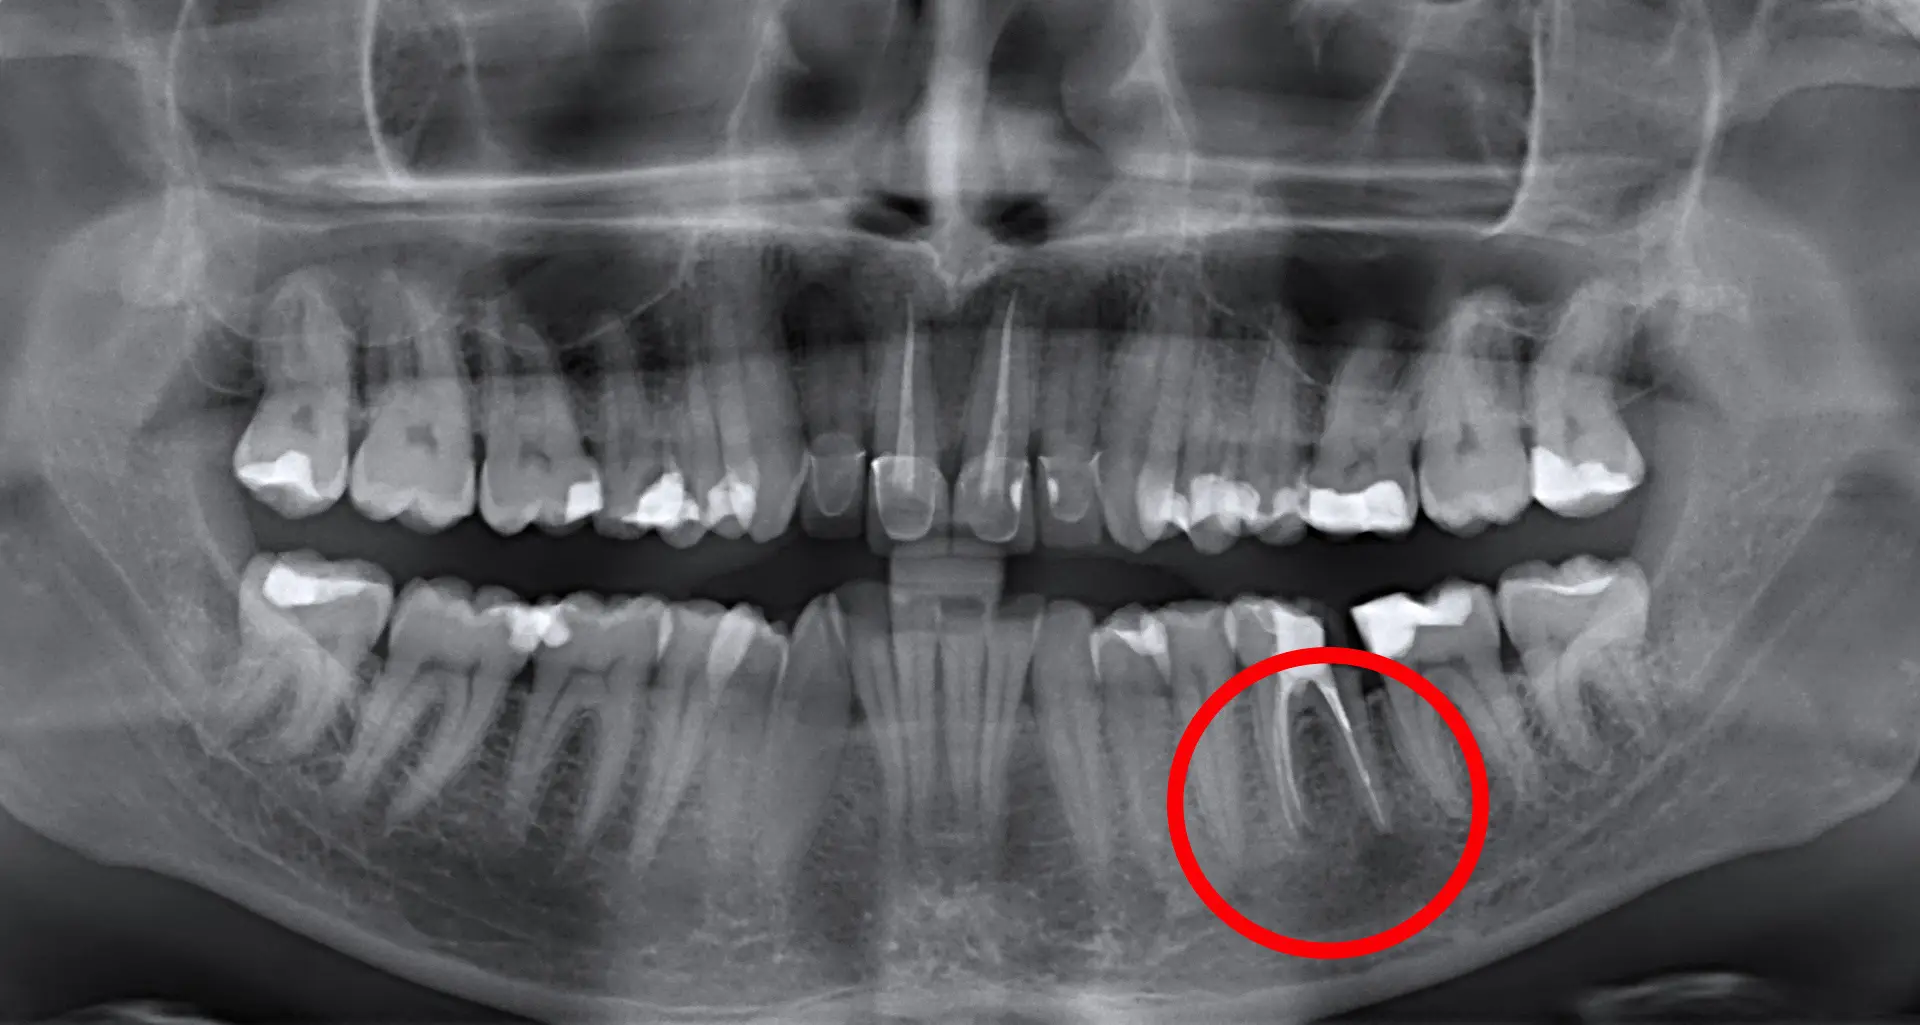

Ako osjećate bol ili oticanje zuba koji je već endodontski liječen, potrebno je zatražiti pomoć stomatologa. Stomatolog će u tom slučaju učiniti RTG snimku tog područja (zuba i okolne kosti) i klinički pregled kako bi se odlučilo je li potrebno napraviti apikotomiju. Korijenski kanali su vrlo složeni, naročito oko vrha korijena. Ponekad nakon endodontskog zahvata zaostane infektivnog debrisa unutar ogranaka kanala. To može dovesti do kasnije reinfekcije i potrebe za apikotomijom. Kod apikotomije se uklanja vrh korijena s upalnim i inficiranim tkivom i punjenjem kanala zapečaćuje se vrh korijena.